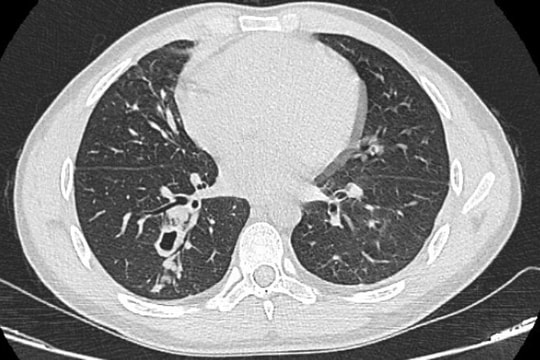

Ho ra máu, đi khám phát hiện sán làm tổ trong phổi

Một năm nay, nam thanh niên mệt mỏi, ho nhiều và ra máu, bác sĩ khám và chẩn đoán nhiễm sán lá phổi.